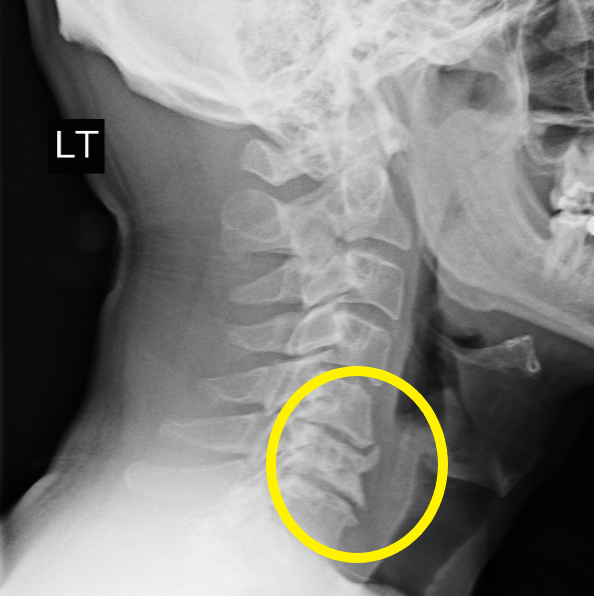

"As you might imagine, I had x-rays and an MRI done. After these were evaluated, I found myself in an office talking to Dr. Hunt, who told me I needed neck surgery. I never expected this and was a little freaked out--not solely because of how much functioning I had lost, but also because the prospect of surgery was pretty nerve-wracking. I spoke to Theresa, who got me scheduled very promptly, and in about two weeks I had ACDF surgery (with three fusions)."

"So my surgery was on 23 Feb 2021 - as I type this it is just over six months later (mid Sept). As far as how I am now, I went from walking with a limp (right leg was very impaired), having weird 'electric shocks' throughout my body, being physically numb over a good bit of my body, and having nearly no hand strength - and now, almost 100% back to normal after six months. I was unable to drive, play the drums, and go to the gym. I actually had trouble standing before surgery!"